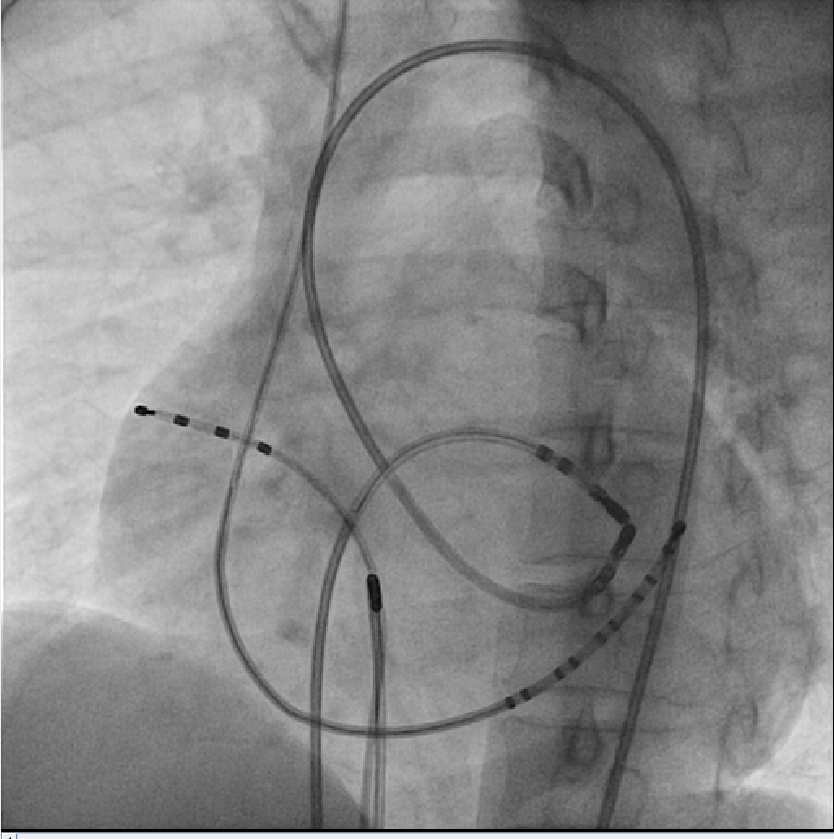

Catheters in the heart

lao.png